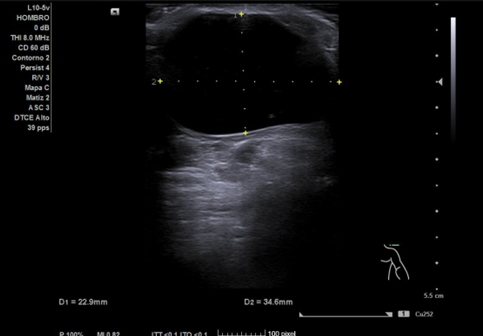

Ecografía hombro izquierdo: se observa una masa de 2,3 x 3,4 cm, anecoica en su totalidad, no tabicada, de bordes bien definidos y sin captación en Doppler.

Pruebas complementarias: Radiografía: No se aprecian líneas de fractura. Corticales íntegras con espacios articulares conservados, sin pinzamientos ni luxaciones. Se observa el quiste ya descrito en la ecografía. Sin lesiones óseas agudas.

Diagnóstico final: quiste sinovial probablemente perteneciente a la articulación acromioclavicular.